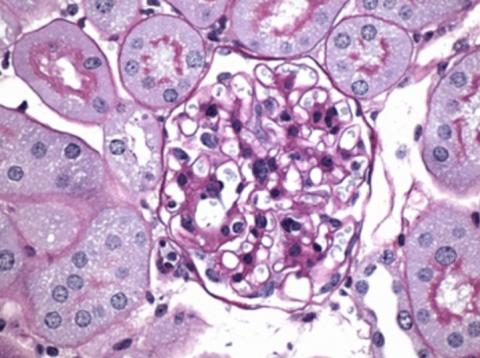

Ce composé, administré à des souris diabétiques a réduit les dommages aux glomérules rénaux (structure plus importante sur visuel ci-dessous) et aux structures environnantes dans le rein, en particulier le tissu cicatriciel (en violet sur visuel).

Ce composé, administré à des souris diabétiques a réduit les dommages aux glomérules rénaux (structure plus importante sur visuel ci-dessous) et aux structures environnantes dans le rein, en particulier le tissu cicatriciel (en violet sur visuel)(Visuel A. Schmidt et al., Sci. Trad. Méd. 13, eabf7084 -2021).